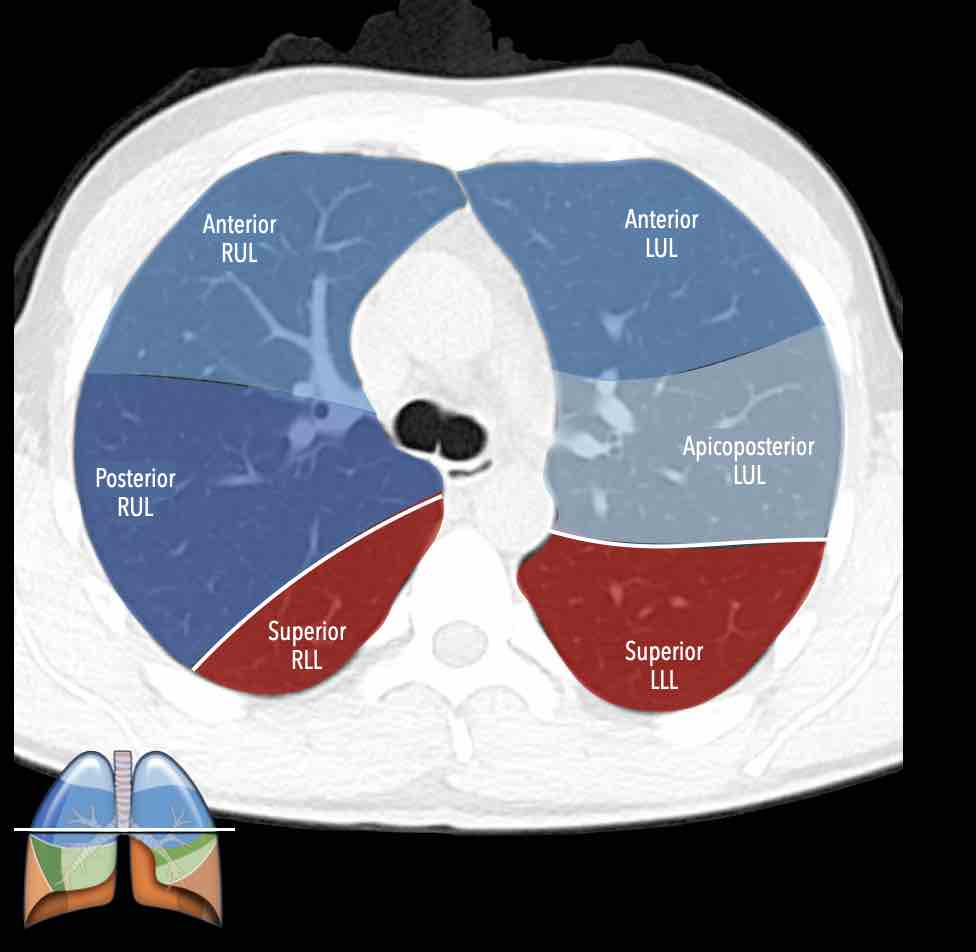

Các phân thùy phổi trên CT

Cuộn qua các hình ảnh để quan sát cách phổi được phân chia thành các phân thùy.